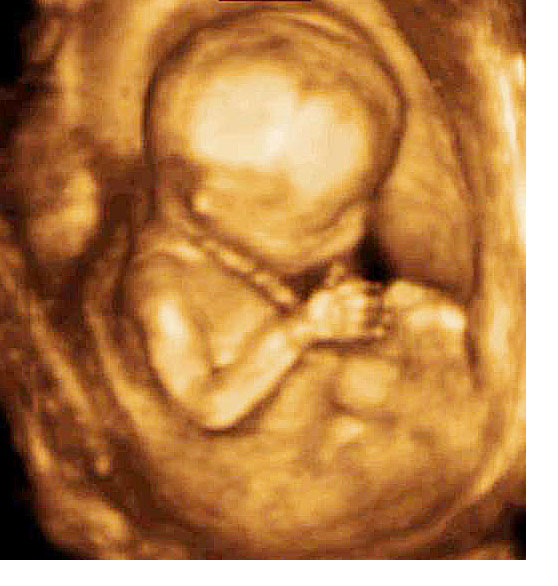

Untuk kehamilan kali pertama, pergerakan bayi selalui dirasai pada kandungan berusia antara 18-22 minggu tetapi kadang kadang ia mungkin mengambil masa lebih lama sehingga 25 minggu. Bagi kandungan kedua dan seterusnya, wanita mungkin boleh merasai pergerakkan seawal 14 minggu. Sekiranya anda berasa risau disebabkan masih gagal untuk merasai pergerakkan bayi anda, jumpa doktor untuk pemeriksaan ultra sound. Bayi selalunya dapat dilihat bergerak aktif walaupun ibu masih belum dapat merasai pergerakannya.

Minggu 12: Bayi anda sepatutnya mula bergerak dengan aktif, tetapi anda mungkin tidak akan dapat merasa apa-apa kerana saiz bayi hanya kira-kira 6 cm panjang.

Minggu 16: Sesetengah wanita hamil akan mula berasa seperti pergerakan rama-rama yang kecil di dalam rahim, tetapi ia tidak semestinya pergerakan bayi.

Minggu 20: Pada ketika anda sudah benar-benar mula merasa pergerakan pertama bayi anda, yang dipanggil “quickening.”

Minggu 24: Bayi kini mempunyai berat kira-kira 500g dan pergerakan itu mula menjadi lebih kuat.

Minggu 28: Bayi anda sering bergerak sekarang dan berat kira-kira 1.2 kg. Beberapa sepakan dan tendangan boleh menyebabkan anda tidak merasa selesa.